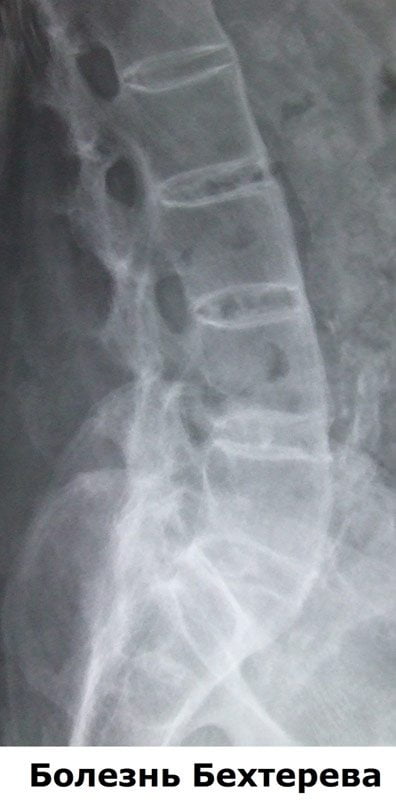

Дополнительной содержательной информацией для врача, служит подтверждение наследственного признака HLA-B27. Подтверждение общей диагностической гипотезы дает рентгенологическая информация, определяющая заметные изменения в крестцово-подвздошном сочленении.

Болезнь Бехтерева при правильном диагностировании имеет классификационные признаки.

| Классификация | Основные осложняющие признаки |

| Предположительная стадия | Рентгенологические снимки не дают подтверждения начала воспалительного процесса |

| Илиосакральная стадия | Начало поражения позвоночного сегмента |

| Стадия окостенения | Частичное окостенение определенного региона позвоночника |

| Поздняя стадия | Окостенение во всех трех (шейном, грудном и поясничном) отделах позвоночника |

Боли в поздней стадии имеют не воспалительный характер, а вызваны лордозом или кифозом, то есть смещением оси позвоночного столба.